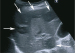

Filmsequenz zu Abbildung 7: Film 3 Kontrastmittelsonographie der Leber im Dualbildmodus (rechts: CEUS; links: normale B-Bild-Sonographie): Die Abszesse zeigen keinen Kontrastmittel- Wash-in oder -Wash-out im Zentrum. |